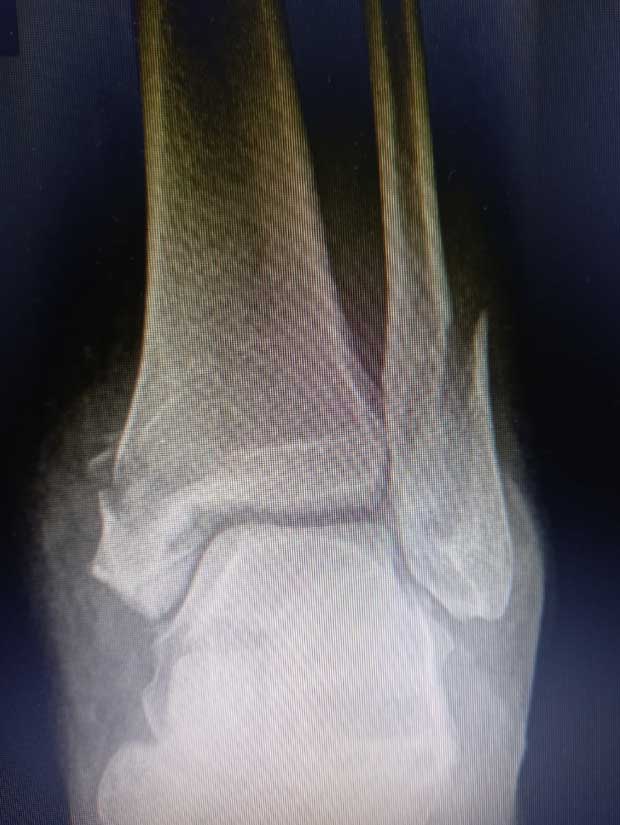

Caso No. 10 - Luxofractura de tobillo

Preoperación

Diagnóstico: Luxofractura de tobillo

Tratamiento: Cirugía: reducción abierta y fijación interna